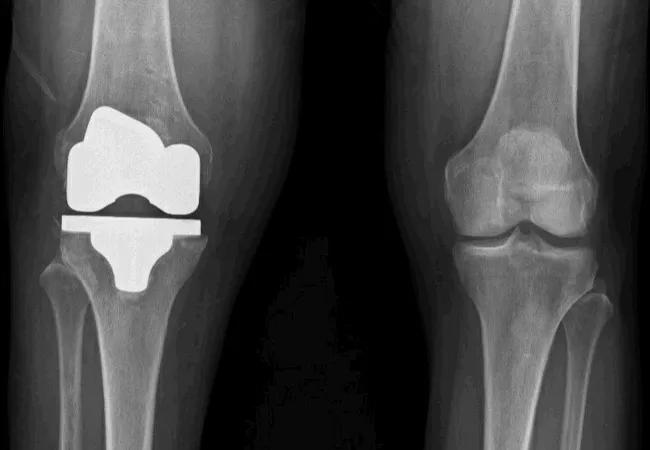

When it comes to the more advanced stages of knee osteoarthritis – and when conservative management has failed – surgical interventions are often utilized. Knee replacements typically provide a predictable outcome, and patients frequently report an improved function and quality of life.

The team utilized a Markov model to simulate a patient scenario, intentionally modeling a patient for whom conservative treatments failed. The model represented a 55-year-old patient with Kellgren-Lawrence grade-II or III knee osteoarthritis undergoing a series of three PRP injections with a one-year delay to TKA versus no delay and TKA from the outset. Outcome metrics included total costs and quality-adjusted life-years (QALYs).

Primary findings reveal that from a healthcare payer perspective, PRP injections resulted in 14.55 QALYs compared with that of 14.63 for TKA, with total healthcare costs of $26,619 and $26,235, respectively. TKA was more cost-effective, producing a higher number of QALYs at a lower cost. This was true from a societal perspective as well.